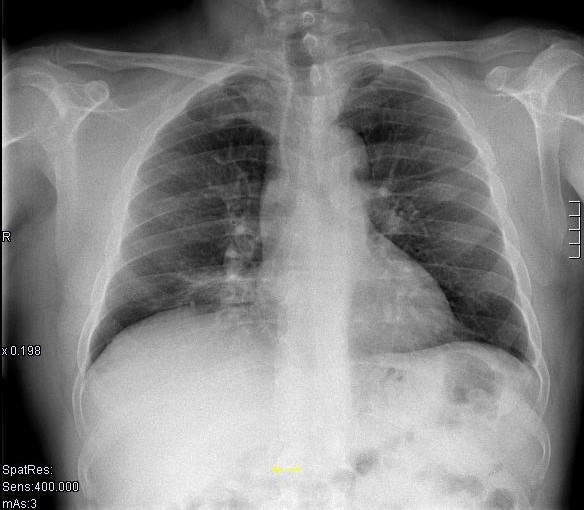

COMENTARIOS: la técnica base para el estudio de la patología torácica es la radiografía simple de tórax. Las dos proyecciones más empleadas son: posterior-anterior y lateral. En nuestro caso, la clínica del paciente sugiere patología pulmonar. Por ello, es recomendable escoger la radiografía simple de tórax como técnica inicial.

El estudio de la radiografía de tórax debe realizarse de forma ordenada. Es útil seguir un esquema lógico para no pasar por alto ninguna alteración. A continuación, está expuesto un esquema estructurado y adecuado para el análisis de las imágenes:

* ¿Se observa el parénquima pulmonar bien aireado y bilateralidad simétrica?

* ¿Se ven nódulos o infiltraciones en el parénquima?

* ¿Son los senos costofrénicos y cardiofrénicos normales?

* ¿Tienen las vértebras dorsales inferiores menor densidad que las superiores?

* ¿Es la silueta cardiomediastínica normal?

* ¿Son los hilios normales y bilateralmente simétricos en tamaño y densidad?

¿Son el esqueleto y las partes blandas regionales normales?

¿Cuáles son los hallazgos radiológicos encontrados en la Rx PA de tórax?